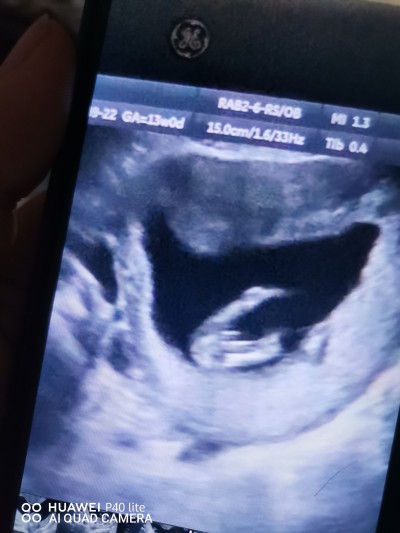

Gebelik tahmin cinsiyet

13

Pipi gördüm sanki :) direk erkek doğdu içime

Doktor erkğe benzyo dedi net bşy dyemm ddi hayrlsnla inşallah

Dr bise demedi mi bacak arası dolu ama bana kordon gbi geldi uzun çünkü haftasına göre bu kadar belli olmaz cinsiyeti haftan küçük daha ama kesin bise diyemeyiz tabi hayırlısyla saglikla gelsin inşallah.

Erkğe benzyo dedi sadece 2 hafta sonra net söylerim dedi

Çıkıntı var erkek gibi saglicakla gelsin

Ben erkeğim diye bağırıyor

Erkek gibi arada birsey görünüyor Allah sağ salim kucağınıza almayı nasip etsin